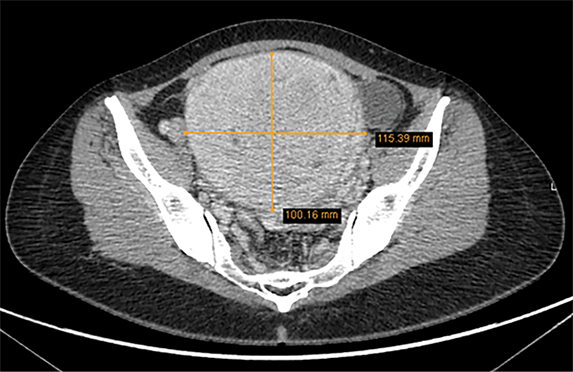

Diagnozei patikslinti nuspręsta atlikti dubens magnetinio rezonanso tomografijos (MRT) tyrimą. MRT metu gimdos priekinėje sienoje pastebėtas didelių matmenų (10x11,5 cm), neaiškių ribų, heterogeniškos struktūros intramuralinis darinys, T2 sekoje – vidutinio intensyvumo signalo, pasižymintis centrinėje dalyje esančiomis nekrozinėmis zonomis ir hemoraginiais intarpais. Skenuojant po intraveninio kontrastavimo, buvo matyti, kad darinys vaskuliarus, kaupia kontrastinę medžiagą, nekrozės srityse turi vaskuliarių struktūrų, ADC signalas izointensinis miometriumui (1,06×10‒3 mm2/s). Gimdos ertmė dėl darinio suspausta ir deformuota, jos kontūrai sunkiai diferencijuojami. Laisvo skysčio pilvaplėvės ertmėje nenustatyta. MRT tyrimo išvada – darinys gimdos kūne, tikėtina, yra lejomiosarkoma (3 pav.).

3 pav. Dubens magnetinio rezonanso tomografija, atlikta diagnozei patikslinti ir gydymo taktikai parinkti